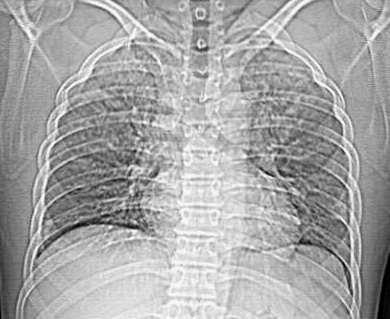

以下是引用ssl1_1在2006-3-2 22:37:00的发言:[br]肺泡蛋白沉积症(外围型)

以下是引用huangaiying1在2006-3-3 16:03:00的发言:[br]双肺弥漫分布的磨玻璃影及小结节影,以双上肺为著,纵隔内未见明显增大的淋巴结影,结合病史,考虑过敏性肺炎

以下是引用guandong在2006-3-4 20:57:00的发言:[br]两肺弥漫分布磨玻璃影,以中外带为主,可见于过敏性肺炎、肺泡蛋白沉着症、农民肺等,但不支持结核。